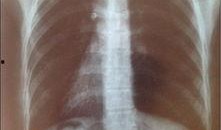

胸片爆料2024年最新,透视健康趋势与疾病预警

最近在网上看到一个超级劲爆的消息,就是2024年的胸片爆料啦!没错,就是那种能让你瞬间了解最新潮流趋势的胸片。今天,我就要带你全...